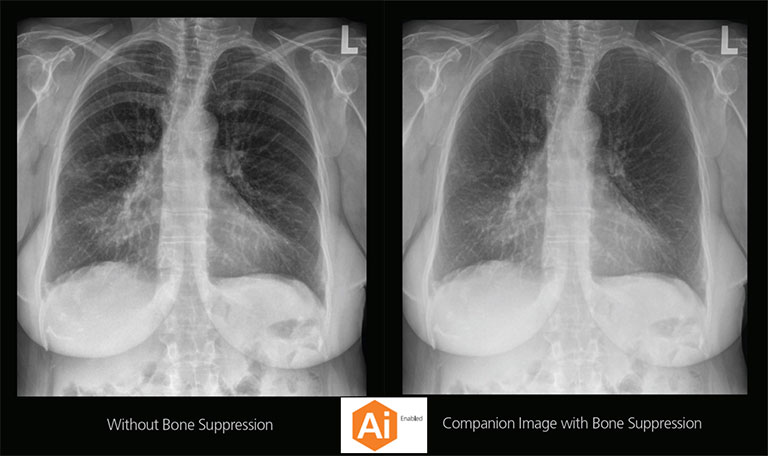

Carestream Introduces New Software Update to Boost Diagnostic Accuracy

Carestream today announced the latest update to its Image Suite V4 Software, MR 11: a series of enhancements to help improve customer confidence and increase diagnostic accuracy [...]

Our Carestream Focus HD 35/43 Retrofit Detectors, powered by Image Suite Software, are an ideal solution to step up to full digital X-ray for customers who simply cannot compromise on image quality. It seamlessly integrates into existing setups, bringing the power of full digital X-ray with minimal disruption and maximum clarity, along with the following benefits: